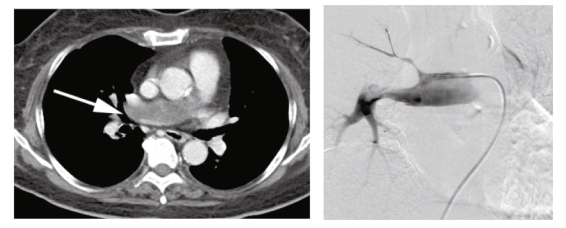

一位72岁女性,有2个月的轻度劳累呼吸困难病史。计算机断层扫描(CT)显示右主肺动脉管腔低衰减缺损(图1)。怀疑肺动脉血栓栓塞。给予阿哌沙班抗凝治疗。然而,经过4周的抗凝治疗后,肺动脉缺损没有改善。

正电子发射断层扫描(PET)显示管腔内缺损处摄取氟-18-氟脱氧葡萄糖(FDG),最大标准摄取值(SUVmax)为4.35,提示为恶性肿瘤。为了确认诊断和治疗方法的选择,使用6 Fr Envoy导管对血管内肿块进行了血管内导管抽吸活检。多次对肿块进行真空抽吸(图2)。组织学检查发现肺动脉肉瘤。未发现远处转移。计划在体外循环下进行右肺切除术,并对肺动脉分叉进行动脉成形术。

图1. 增强CT扫描显示右主肺动脉有肿瘤(箭头)

图2. 肺血管造影显示右主肺动脉肿瘤。将导管附着在填充缺损处,并进行真空抽吸